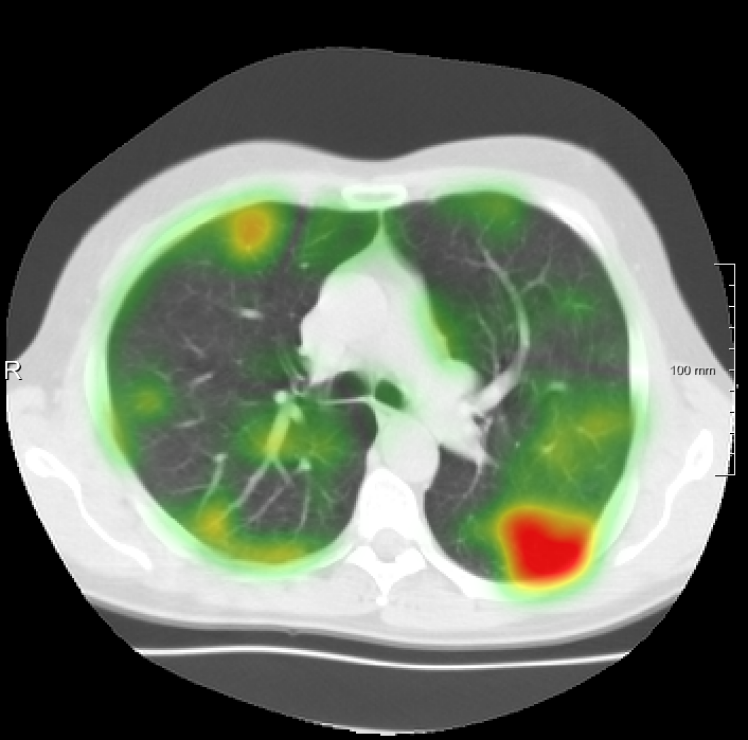

For the DIR-Lab-4DCT database, a comparison between RegNet and affine, B-spline (three resolutions), an advanced conventional registration method using sliding motion (Berendsen et al., 2014) and three other CNN-based methods (Eppenhof and Pluim, 2018; de Vos et al., 2019; Sentker et al., 2018) is available in Table IV. It can be seen that training with “S+M” improved performance slightly with respect to just “S”. Adding the respiratory motion category improved performance substantially, as these are inhale-exhale pairs; this is predominantly caused by the patients where the TRE after affine registration was still quite large. An example visualization is also available in Fig. 5(f), showing that adding the respiratory motion category can align images better in the diaphragm region. The advanced conventional registration method that leverages sliding motion (Berendsen et al., 2014) is still better than RegNet. Note that RegNet was not trained on the DIR-Lab-4DCT data, similar to Eppenhof and Pluim (2018); Sentker et al. (2018). However, de Vos et al. (2019) and Eppenhof and Pluim (2018)-DIR methods were trained on the same database but using cross-validation to report the results. Also note that the results reported in Sentker et al. (2018) are averaged over all phases of DIR-Lab-4DCT (T00 to T10), while the results of other CNN methods (including RegNet) are reported between the maximum inhale and maximum exhale phase (T00 and T50). These reported results are therefore likely somewhat better than the results for T00 and T50 only.